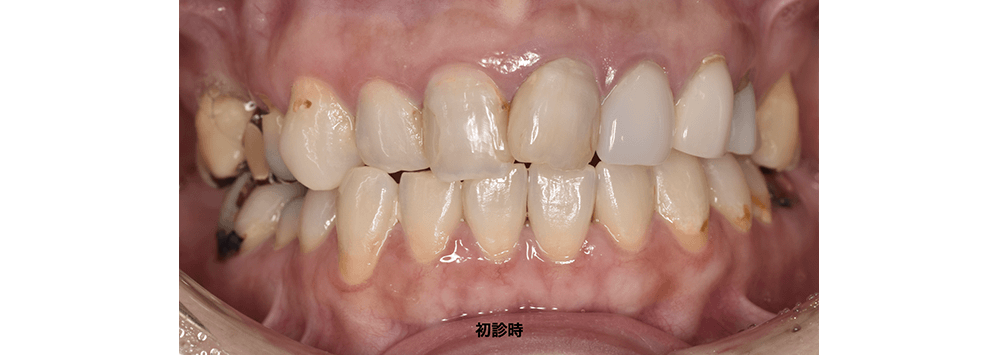

症例4

前歯の形・色の改善を目的として矯正治療とセラミック治療を行った症例(30代女性)

治療前

症例4 治療前

症例4 治療前2

患者主訴

• 前歯の色が気になる

• 歯並びを整えたい

治療詳細

以前から前歯の歯並びや見た目にコンプレックスがあり当院へご相談いただきました。

診査診断

カウンセリング後に模型分析・シミュレーションを行いました。診断の結果、前歯の形や色だけでなく歯並びやかみ合わせにも問題があることがわかりました。セラミック治療だけでは多く歯を削る必要があるうえに、歯の形のバランスが取れないことが分かりました。その結果、見た目と機能、長期に安定する治療を希望されましたので矯正治療とセラミック治療を行うことになりました。